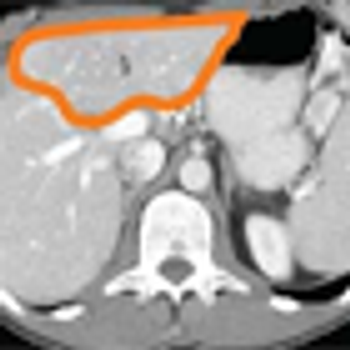

This slide show features a CT image, and pathology images of gastrointestinal stromal tumors (GISTs) arising in the stomach using H&E, CD34, and c-Kit staining.